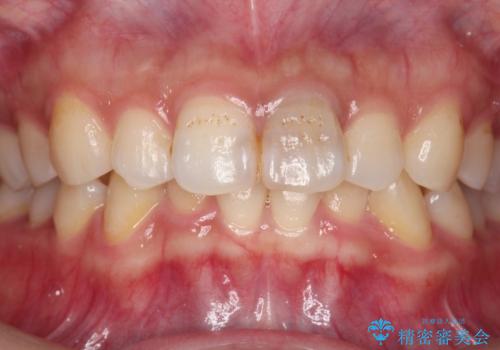

- 前歯部の歯ぐきが腫れたり、にきびのようなものが繰り返しできる。と不快症状を訴えて来院されました。

X線検査を行い診断的な小手術を行ったところ、歯に亀裂があり修復が不可能な状態であることがわかりました。